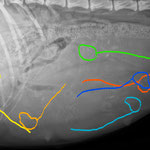

Hündinnen tragen normalerweise 63 Tage. Da man aber (ohne aufwändige medizinische Tests) den genauen Zeitpunkt des Eisprungs nur nach dem Datum der Deckungsbereitschaft der Hündin abschätzen kann, bleibt auch der voraussichtliche Wurftermin nur eine Schätzung. Erst ab dem 25. Trächtigkeitstag kann man mittels Ultraschall feststellen, ob die Hündin überhaupt trägt. Ihr äusserlich ansehen kann man das sogar erst ab ungefähr dem 40. Tag. Es könnte ja aber auch immer noch eine Scheinträchtigkeit sein. Gewissheit gibt ein Röntgen, das ab dem 45. Tag gefahrlos gemacht werden kann.

Nach einer Stunde nach der ersten Geburt war nichts weiter passiert, keine Wehen nichts. Nach 1.5 Stunden wurden wir langsam nervös und sind nachlesen gegangen, wie lange sowas höchstens dauern darf. 4 Stunden stand dort. Na ja, da hatten wir ja noch etwas Zeit. Aber nein, uns war nicht wohl dabei. Einfach zuwarten und dann vielleicht Haria und Welpe 1 ins Auto laden und zum Tierarzt fahren und dann womöglich Kaiserschnitt und dann vielleicht tote Welpen weil zu lange gewartet..... Nein, lieber nicht, da haben wir doch noch ein paar Möglichkeiten, dieser Geburt evtl. etwas nachzuhelfen. Also Handschuhe anziehen und "nachschauen". Bei Steissgeburten kann es sein, dass ein Beinchen quer liegt und der Welpe deshalb gar nicht hinaus kann. Oder das Kleine sonst irgendwie quer liegt. Oder tot ist. Aber mit buchstäblichem Fingerspitzengefühl gelang es uns schliesslich, beide Beinchen nebeneinander zu legen und den Geburtskanal etwas zu dehnen. Gleichzeitig löst diese Stimulation Presswehen aus, und schliesslich rutschte Nr. 2 hinaus. Und lebt! Wieder ein heller Bub. Nr. 3, schwarz und schon wieder ein Bub, lag offenbar schon längst bereit und rutschte gleich nach. Haria hatte also grad viel zu tun, und uns gings mit wägen, notieren und beobachten ob alles in Ordnung ist nicht anders. Es ist immer wieder erstaunlich, wie die Welpen nach der Geburt nach kurzer Erholungszeit bereits auf Nahrungssuche gehen und sehr treffsicher die Zitzen ihrer Mutter finden. Der Geruchssinn ist auch der einzige, der von Anfang an genau für diesen Zweck funktioniert. Einen Schoppen nehmen die Welpen in diesem Anfangsstadium nicht, weil der nicht nach Mama riecht. Ausserdem ist diese allererste Milch der Mutter, Kolostrum genannt, ja auch enorm wichtig. Nr. 4 und 5 liessen zwar auch auf sich warten, aber es lag im Rahmen. Haria hatte einfach kaum Wehen. Und dann Nr. 6. Wenn Nr. 2 schon schwierig war, dann war Nr. 6 fast unmöglich. Haria presste ein wenig, das Welpchen wurde sichtbar, dann rutschte es wieder hinein. So ging es die längste Zeit. Auf keinen Fall wollen wir nun alles in Auto verfrachten und zum Tierarzt fahren. Das müssen wir jetzt hinkriegen, Haria bitte bitte mach mit, wir wissen ja, dass du unendlich müde bist. Aber wenn die Blase, in der das Ungeborene sich befindet, sich bereits vor der Geburt öffnet, wird das für den Welpen sehr rasch lebensgefährlich. Er kann ertrinken oder ersticken. Man kann also nicht einfach mal abwarten. Es wurde buchstäblich zu einer Zangengeburt, obwohl wir natürlich ausser unserer Hände keine weiteren "Werkzeuge" benutzten. Papa Walendil, der ja die ganze Nacht auch mit im Wurfzimmer war, wurde ebenfalls nervös und begann zu fiepen, wollte irgendwie helfen. Dann endlich war die Kleine da und lebte - aber atmete zu lange nicht. Also weiter mit stimulieren der Lunge mit vorsichtig Luft hineinblasen sowie eventuelle Flüssigkeiten hinaussaugen.. Gruusig? Nein, nicht in dem Moment. Dann auf einmal ein Luftschnappen, und nochmal, und nochmal. Und so gings weiter: die Kleine atmete nicht richtig, sie schnappte nur nach Luft. Fast zwei Stunden ging das so, bis die Lungen in Kombination mit der Schluckbewegung beim Trinken langsam den richtigen Rhythmus fanden. Unterdessen kam dann nach völlig überraschend Nr. 7, weil, im Röntgenbild hatten wir ja nur 6 Welpen gesehen. Und als dann alles in Ordnung war, wir nach dieser Freinacht einen Kaffee tranken und uns einen Moment aufs Ohr legen wollten, begannen wir zuerst an uns selbst zu zweifeln, als plötzlich nochmal so ein nasses Würmchen hinter Haria lag. Wieso ist der jetzt wieder nass? Es waren doch schon alle trocken? Nach mehrmaligem Zählen wurde dann deutlich, dass Haria noch eines rausgedrückt hatte, einfach so noch zum Dessert. Es schien so gar, als ob sie es zuerst selber nicht bemerkt hätte, wir mussten sie nämlich darauf aufmerksam machen, die Nabelschnur durchzutrennen und überhaupt sich um diesen Nachzügler auch noch zu kümmern. Aber Haria ist eine so hingebungsvolle Hundemama, natürlich hat sie sich um alle ihre Kinder rührend gekümmert. Und Walendil machte ab und zu Anstalten, ihr dabei zu helfen. Aber ein Papa ist da nicht so geschickt mit Neugeborenen, das wusste er und das wusste auch Haria. Es brauchte nur einen Blick von ihr, damit er den gebührenden Abstand einhielt und es bei den guten Absichten bewenden liess.